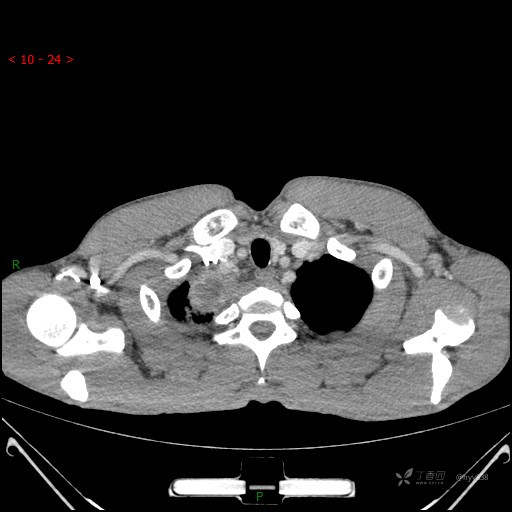

辅助检查:CT

胸部CT平扫